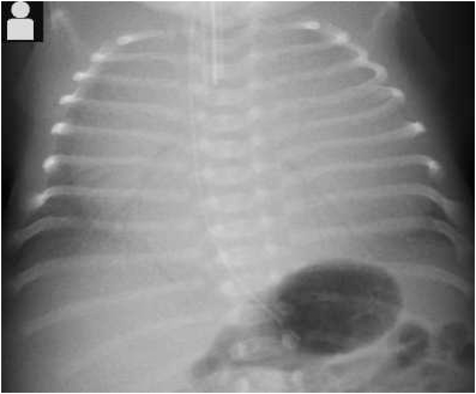

胸部X線:心胸郭比80.3%,Bomsel分類IV度(Fig. 2

Pediatric Cardiology and Cardiac Surgery 33(3): 215-220 (2017)

Fig. 2 Chest X-ray showed severe cardiomegaly and more extensive air bronchogram at birth